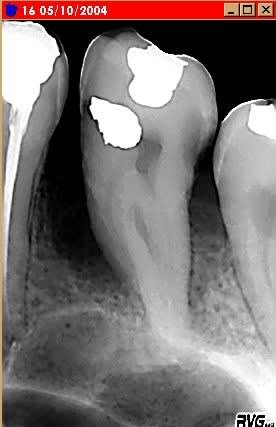

Seule la 16 est touchée. Cette fonte alvéolaire peut elle être due au phénomène diasthème-bourrage-carie distale + gingivite = parodontite ?

traitement, pronostic ?

A noter : au microscope, on voit des spirokets ( je sais, cela ne s'écrit pas comme ça ! ), des batonnets de différentes longueurs mobiles et des truc qui ressemble à des amibes, mais immobiles ( est ce possible ? )

Il y a aussi un encombrement antérieur avec 15 25 dévitalisées en mauvais état. La patiente est ok pour odf, donc on vire 15 25, mais je retombe sur le problème de la 16 qui ne forme pas un ancrage très solide ( euphémisme ). Peut-être un ancrage par mini implant vestibulaire ?

pour moi il s'agit d'une parodontite liée sans doute à un bourrage alimentaire . As tu regardé l'occlusion qui pourrait être un facteur aggravant . La voila les cas ou je ne sonde pas trop car je peux récupérer du parodonte quoi que la il doit y avoir une atteinte inter radiculaire . Le microscope te montre des spirochètes ce qui témoigne au minimum d'une gingivite et d'une inflammation du parodonte ( saignement ) . Des amibes tu peux en trouver immobiles ou mobiles si les conditions d'anaérobioses sont marquées et pour moi si le site est en phase de dégradation .

- traitement antiseptie plus litho progressivement + controle de l'occlusion . Le probleme pour cette dent est qu'il y a sans doute une atteinte inter radiculaire avec une anomalie . Je ne suis pas persuadé aux vues de la rx que tu puisses stabiliser sur le long terme cette dent ( les atteintes IR dans ce cas......). Attention le sinus n'est pas loin. Ne prend pas trop le risque de perdre d'avantage d'os pour compliquer ensuite ton approche si tu veux mettre un implant ( si la 16 n'est pas récupérable tu fais quoi )

Tu n'indiques pas le degré de mobilité de la dent, mais quoi qu'il en soit je ne parierai pas un kopeck sur sa survie à court- moyen terme quelle que soit l'étiologie, le diagnostic et la thérapeutique mis en place.

Il me semble entrevoir une début de zone radioclaire masquée par la radioopacité de la dent en forme semi circulaire qui se termine en distal ce qui laisse supposer une destruction osseuse beaucoup plus importante que la radio le laisse entrevoir(c'est importer d'essayer de deviner ce que la radio nous cache; importante lyse osseuse palatine ou vestibulaire). d'autre part la conicité radiculaire est un facteur hyperdéfavorable.